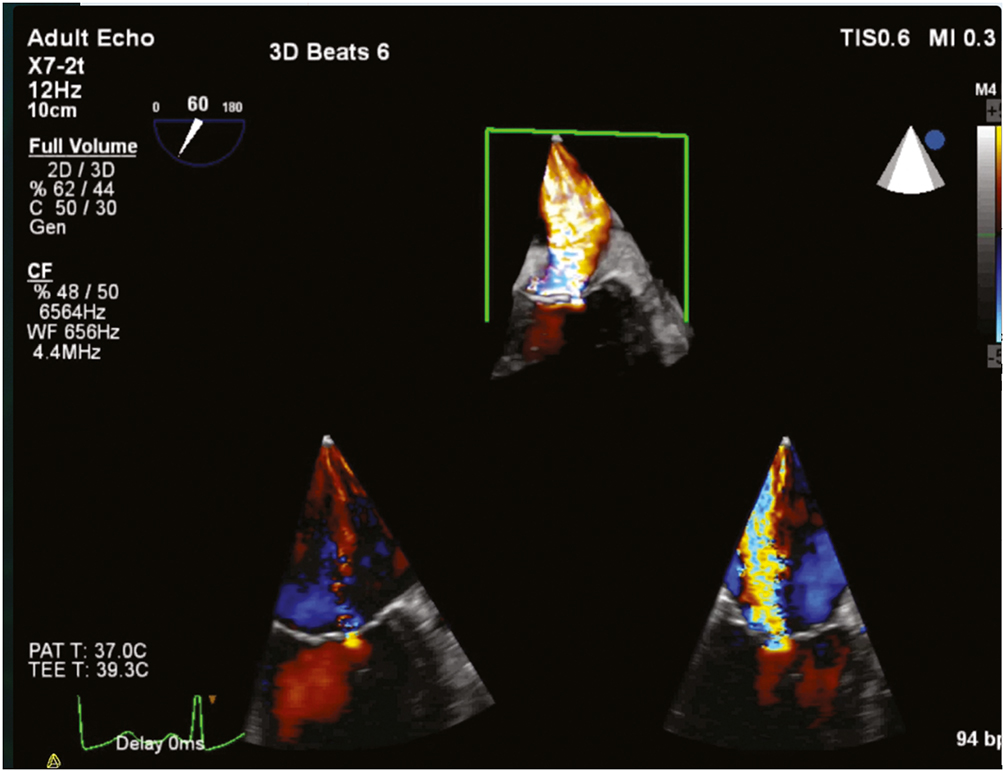

Catheterization criteria for AI rely on the qualitative estimation of the regurgitation volume and estimation of left ventricular size and ejection fraction. Similar quantification can be made from Doppler color echocardiography-derived data. The width of the regurgitant jet at the level of the AV can be compared to the width of the LVOT. A ratio of more than 0.6 corresponds to severe AI (Figure 7.17; Video 7.2). Another sign of severe AI is diastolic flow reversal of the descending thoracic aorta, as observed on spectral Doppler.